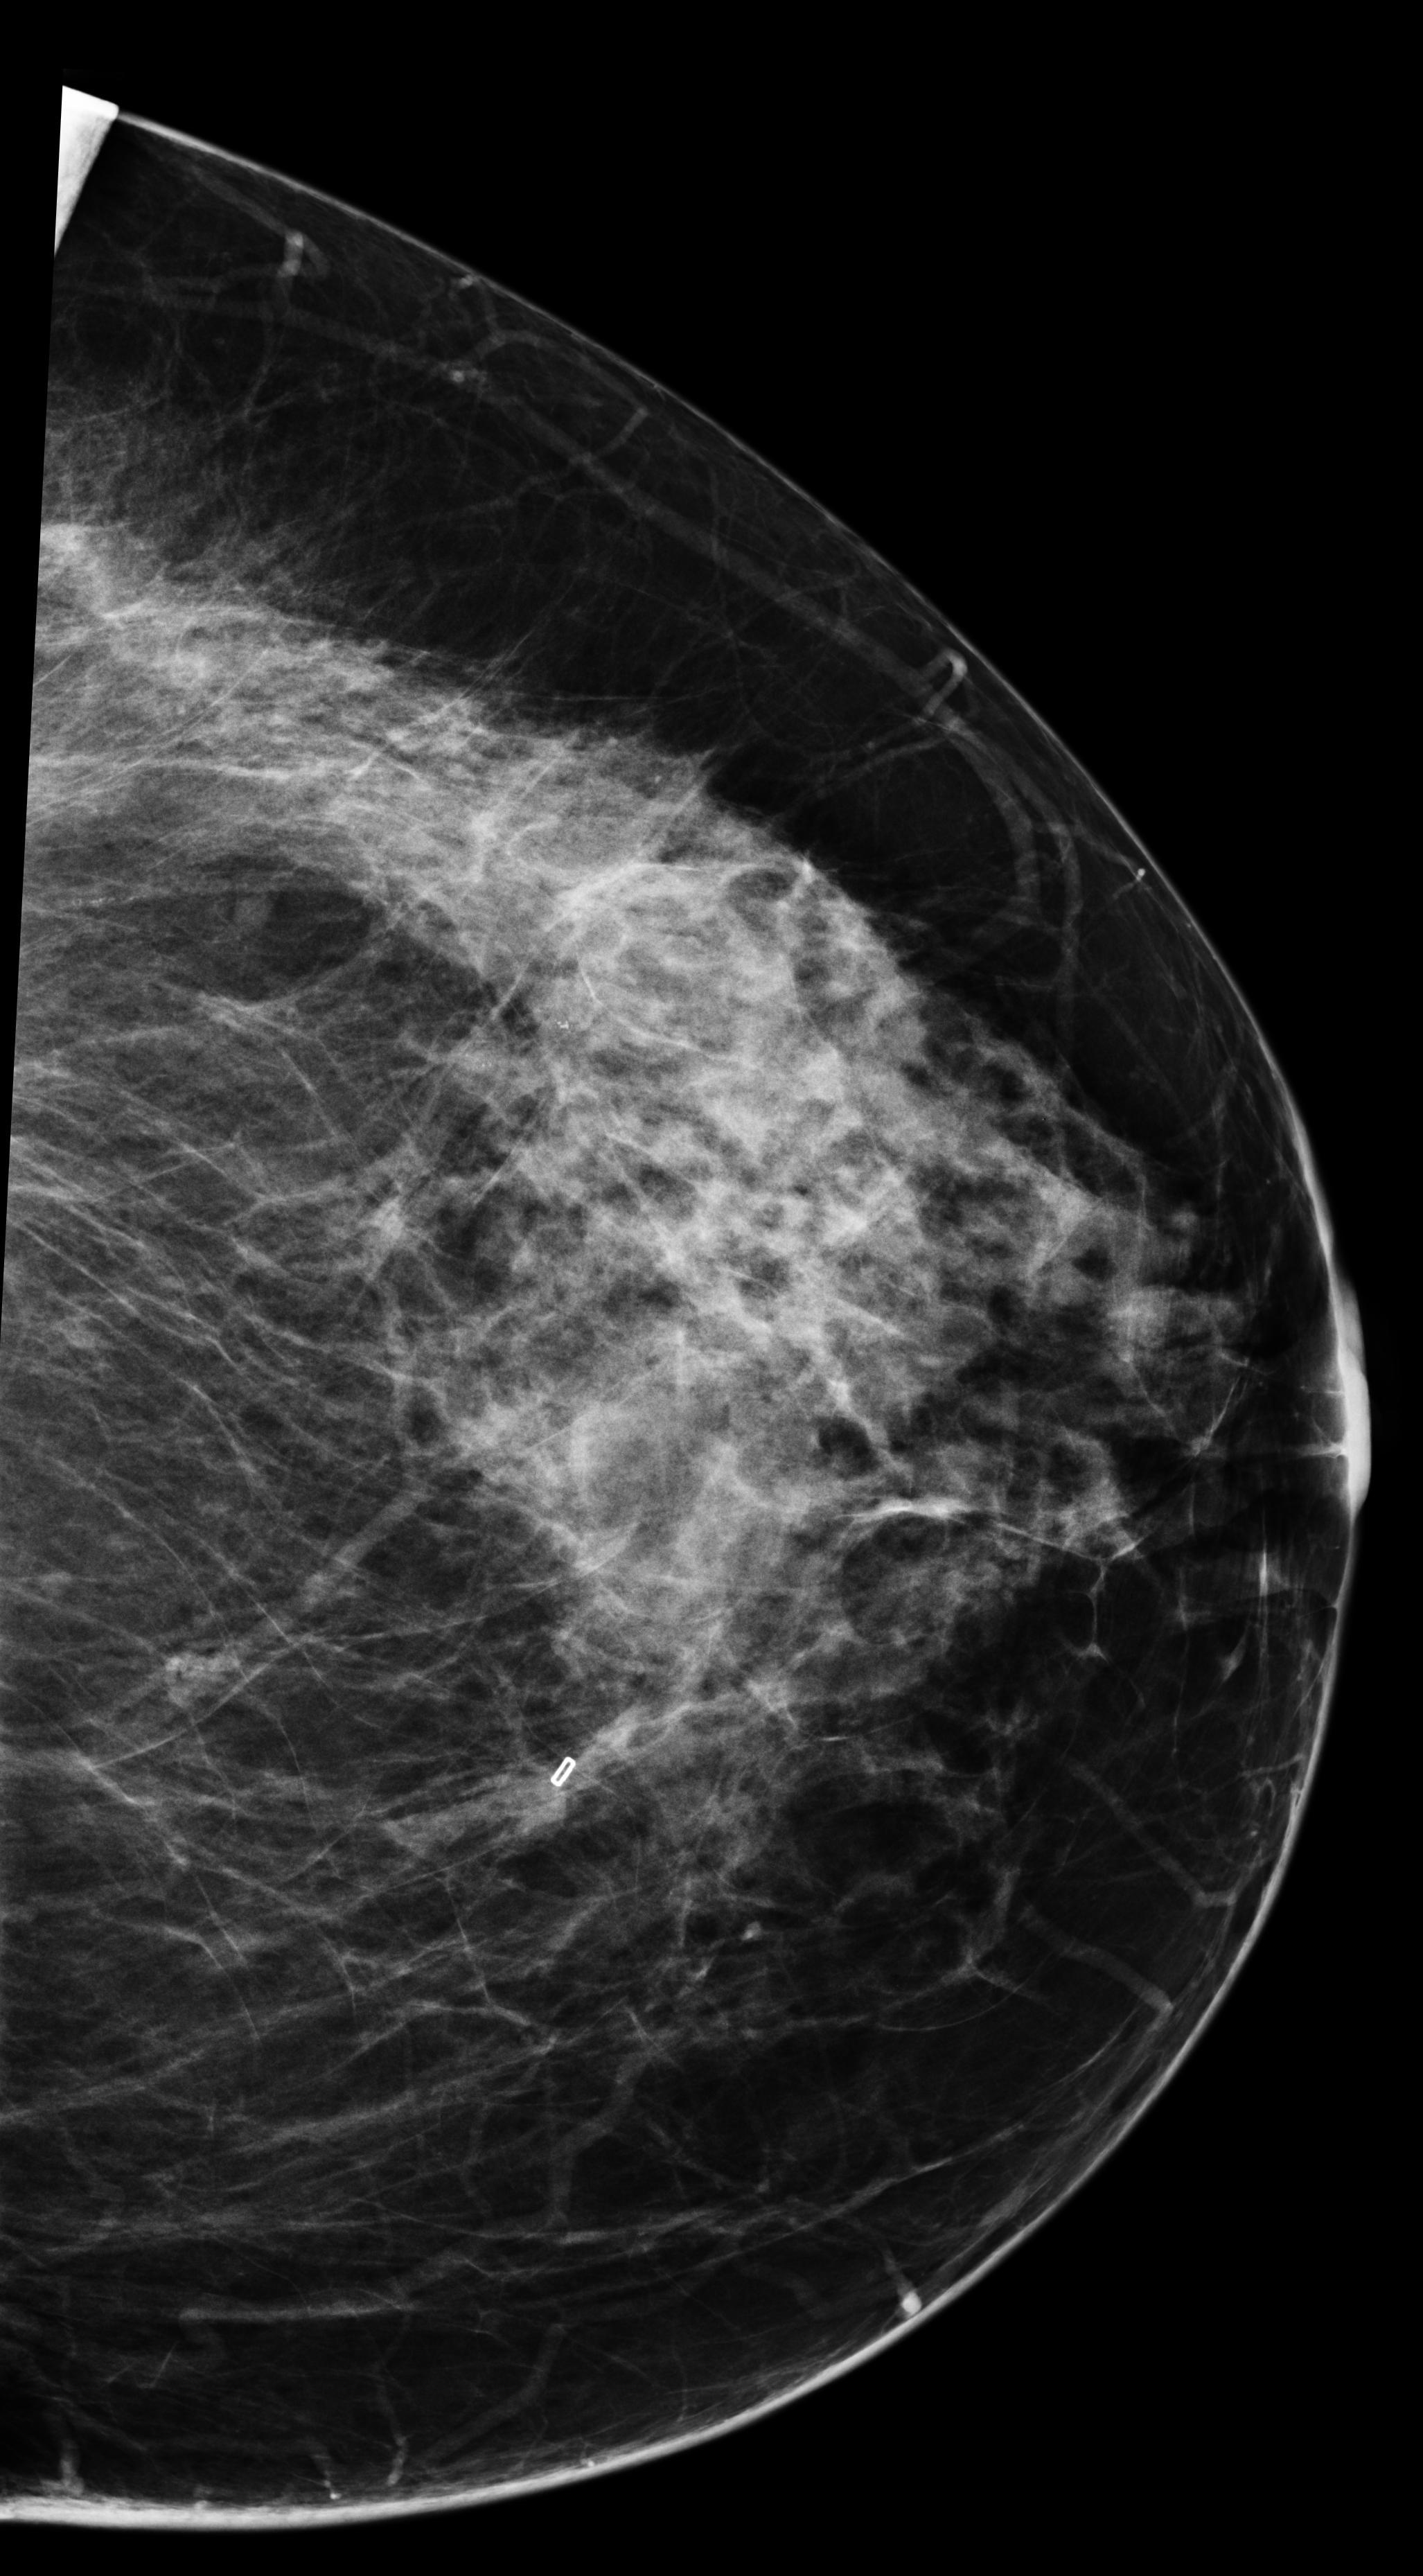

[\capbeside\thisfloatsetupcapbesideposition=left,top,capbesidewidth=6cm]figure[13cm] prior latest highlight prior latest L-CC Refer to caption Refer to caption Refer to caption L-CC Refer to caption Refer to caption L-MLO Refer to caption Refer to caption Refer to caption L-MLO Refer to caption Refer to caption (a) (b)

Figure 3: Test examples where AlignLocalCompare performs better than the single-exam baseline. A breast with a malignant finding shown in (a) (malignant finding is highlighted with red) and one with a benign lesion shown in (b). AlignLocalCompare predicts malignancy with 0.97 probability for (a) and 0.04 for (b), whereas the baseline predicts 0.73 for (a) and 0.24 for (b). There is about a year gap between two exams for both patients.